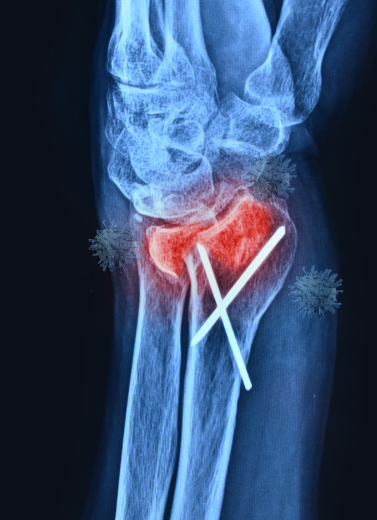

Minimally Invasive Fracture Fixation

Plating & Nailing Techniques

Ilizarov External Fixation (for limb lengthening & deformities)

All surgeries are performed with infection-controlled OTs, digital X-ray support, and post-op rehab planning.

We treat each trauma case with urgency and care, beginning with imaging (X-ray/CT), followed by a personalized treatment plan. Whether surgical or conservative, our aim is quick stabilization, early mobilization, and pain control.